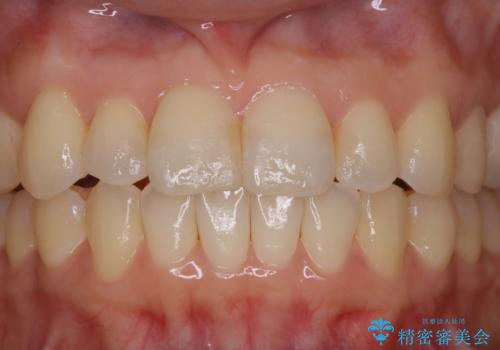

矯正治療とセラミック治療が終了後のPMTC

- 矯正治療とセラミック治療の総合治療が終了したため、クリーニングをしっかりとしてからメンテナンスに入りたいとのことでした。PMTC30分コースを行いました。

矯正治療が終わり、せっかくきれいになった歯並びも、虫歯・歯周病などになってしまっては元も子もありません。

矯正治療やセラミックなどによる被せ物の治療終了のタイミングではクリーニングを行い、汚れや着色の除去、歯と歯の間・歯と歯肉との境目などのケアをしっかりすることをおすすめしています。

ご自身での歯ブラシ・セルフケアを行うと同時に、定期的なクリーニング(PMTC)を行うことで、いつまでも健康な歯を保つことができます。